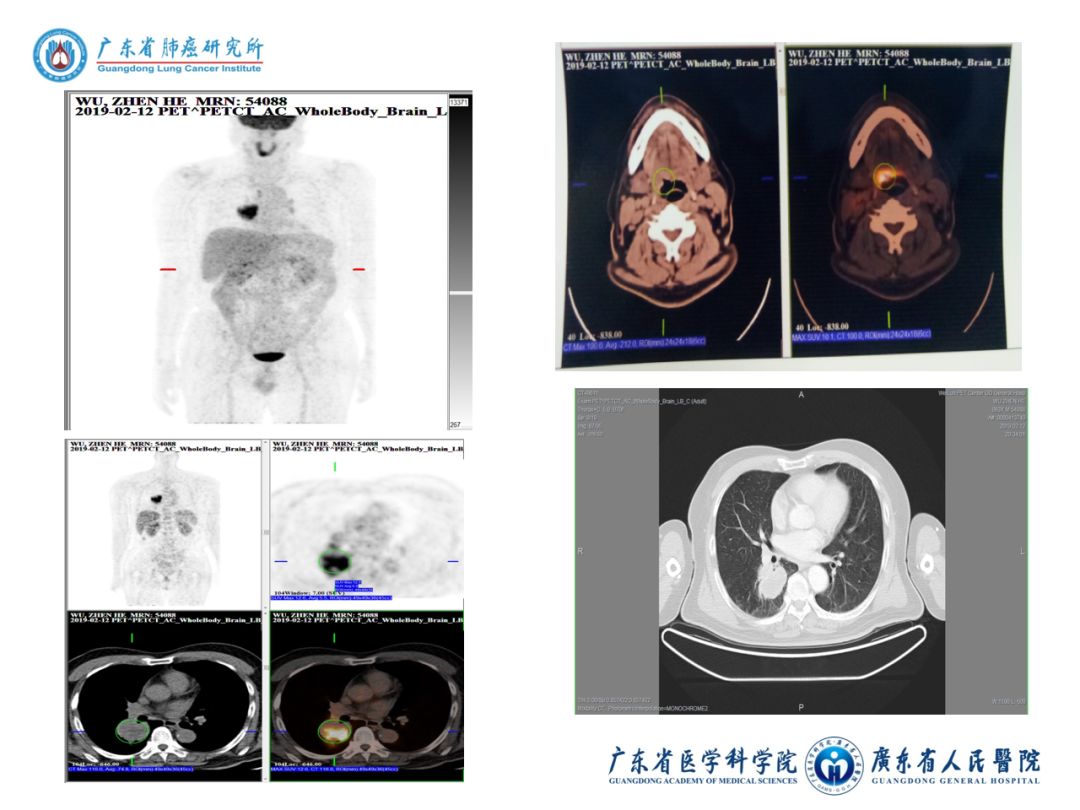

3)2019-02-12我院PET/CT:

① 舌根部肿块2.1cm×1.4cm,SUVmax10.1,考虑舌恶性肿瘤。

② 右肺下叶肿块5.0cm×4.6cm,SUVmax12.6,考虑原发肺癌;R2淋巴结增大,SUVmax5。

8)2019-02-12 广东省人民医院PET/CT:

① 舌根部肿块并溃疡形成,葡萄糖代谢增高,考虑舌恶性肿瘤。

② 右肺下叶背段肿块,糖代谢增高,考虑原发肺癌;纵隔和右肺叶间增大淋巴结,葡萄糖代谢增高,考虑转移性淋巴结。

③ 18F-FDG-PET/CT体部扫描未见其他部位恶性肿瘤代谢影像。

④ 右侧上颌窦、双侧筛窦炎。

⑤ 甲状腺右叶低密度影,葡萄糖代谢未见增高,考虑良性病变。

⑥ 左肺上叶钙化灶;左肺上叶舌段及右肺下叶少量条索。

⑦ 左心室室壁瘤。

⑧ 胆囊结石。

⑨ 前列腺钙化。

⑩ 垂体糖代谢增高,不除外垂体瘤,建议MRI检查。

图表资料